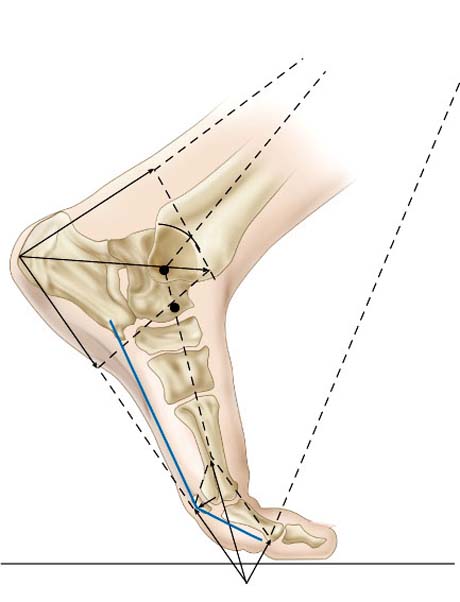

Το πόδι διαθέτει δύο σημαντικές λειτουργίες την ικανότητα διαχείρισης του σωματικού βάρους καθώς και την ικανότητα προώθησης αυτού. Οι δύο αυτές λειτουργίες απαιτούν υψηλή σταθερότητα. Επίσης το πόδι έχει σημαντική ελαστικότητα για να μπορεί να προσαρμόζεται σε ανώμαλες επιφάνειες.

Η ποδική καμάρα βρίσκεται στο έσω χείλος του ποδιού και δημιουργείται από τη πτέρνα, τον αστράγαλο, το σκαφοειδές οστούν, τα σφηνοειδή οστά καθώς και τα τρία πρώτα μετατάρσια. Η ιδιαίτερη αυτή κατασκευή υποστηρίζεται από τους συνδέσμους και τους μύες προσδίδοντας στο πόδι την απαραίτητη ελαστικότητα διευκολύνοντας τη βάδιση, το τρέξιμο και την αλτική ικανότητα του ανθρώπου.

Η εξαιρετική γεωμετρία του ποδιού προσδίδει τη δυνατότητα στον άνθρωπο για την επιτέλεση απλών αλλά και πολύ σύνθετων δραστηριοτήτων με τη χαμηλότερη ενεργειακή κατανάλωση η οποία μεταφράζεται ως η λιγότερο δυνατή κόπωση κατά τη προσπάθεια.